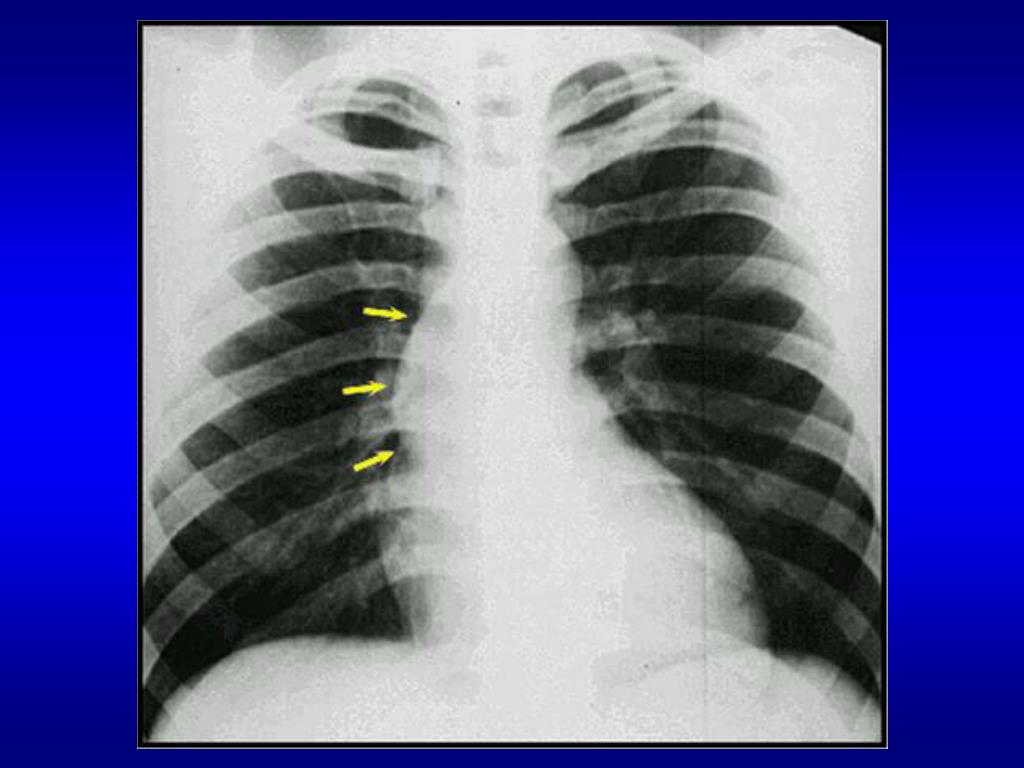

20. x-ray